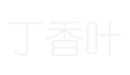

图-2. 轴向(A)和冠状(B)颞骨计算机断层扫描显示乳突浑浊,伴有骨隔缺失。 注意皮质骨和耳后液采集中的缺陷(箭头)。